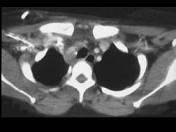

男,33岁,车祸后10余天,请结合影像学检查,选出最可能的诊断 ( )A.纵隔畸胎瘤B.胸内甲状腺肿C.胸腺瘤D.淋巴瘤E.纵隔血肿

问题 男,33岁,车祸后10余天,请结合影像学检查,选出最可能的诊断 ( )

选项 A.纵隔畸胎瘤 B.胸内甲状腺肿 C.胸腺瘤 D.淋巴瘤 E.纵隔血肿

答案 E